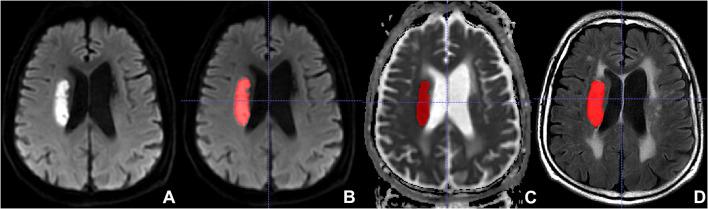

At present, it is still challenging to predict the clinical outcome of acute ischemic stroke (AIS). In this retrospective study, we explored whether radiomics features extracted from fluid-attenuated inversion recovery (FLAIR) and apparent diffusion coefficient (ADC) images can predict clinical outcome of patients with AIS. Patients with AIS were divided into a training ( = 110) and an external validation ( = 80) sets. A total of 753 radiomics features were extracted from each FLAIR and ADC image of the 190 patients. Interquartile range (IQR), Wilcoxon rank sum test, and least absolute shrinkage and selection operator (LASSO) were used to reduce the feature dimension. The six strongest radiomics features were related to an unfavorable outcome of AIS. A logistic regression analysis was employed for selection of potential predominating clinical and conventional magnetic resonance imaging (MRI) factors. Subsequently, we developed several models based on clinical and conventional MRI factors and radiomics features to predict the outcome of AIS patients. For predicting unfavorable outcome [modified Rankin scale (mRS) > 2] in the training set, the area under the receiver operating characteristic curve (AUC) of ADC radiomics model was 0.772, FLAIR radiomics model 0.731, ADC and FLAIR radiomics model 0.815, clinical model 0.791, and clinical and conventional MRI model 0.782. In the external validation set, the AUCs for the prediction with ADC radiomics model was 0.792, FLAIR radiomics model 0.707, ADC and FLAIR radiomics model 0.825, clinical model 0.763, and clinical and conventional MRI model 0.751. When adding radiomics features to the combined model, the AUCs for predicting unfavorable outcome in the training and external validation sets were 0.926 and 0.864, respectively. Our results indicate that the radiomics features extracted from FLAIR and ADC can be instrumental biomarkers to predict unfavorable clinical outcome of AIS and would additionally improve predictive performance when adding to combined model.

目前,预测急性缺血性卒中(AIS)的临床结局仍具有挑战性。在这项回顾性研究中,我们探讨了从液体衰减反转恢复(FLAIR)和表观扩散系数(ADC)图像中提取的影像组学特征是否能够预测AIS患者的临床结局。AIS患者被分为训练集(n = 110)和外部验证集(n = 80)。从190例患者的每幅FLAIR和ADC图像中总共提取了753个影像组学特征。采用四分位数间距(IQR)、Wilcoxon秩和检验以及最小绝对收缩和选择算子(LASSO)来降低特征维度。六个最强的影像组学特征与AIS的不良结局相关。采用逻辑回归分析来选择潜在的主要临床和传统磁共振成像(MRI)因素。随后,我们基于临床和传统MRI因素以及影像组学特征开发了多个模型来预测AIS患者的结局。对于训练集中预测不良结局[改良Rankin量表(mRS)>2],ADC影像组学模型的受试者操作特征曲线(AUC)下面积为0.772,FLAIR影像组学模型为0.731,ADC和FLAIR影像组学模型为0.815,临床模型为0.791,临床和传统MRI模型为0.782。在外部验证集中,ADC影像组学模型预测的AUC为0.792,FLAIR影像组学模型为0.707,ADC和FLAIR影像组学模型为0.825,临床模型为0.763,临床和传统MRI模型为0.751。当将影像组学特征添加到联合模型中时,训练集和外部验证集中预测不良结局的AUC分别为0.926和0.864。我们的结果表明,从FLAIR和ADC中提取的影像组学特征可以作为预测AIS不良临床结局的有用生物标志物,并且添加到联合模型中时还会提高预测性能。